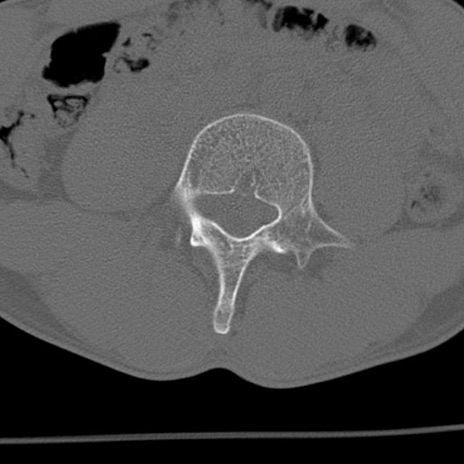

症例3 腰椎CT(横断像)

腰椎CT